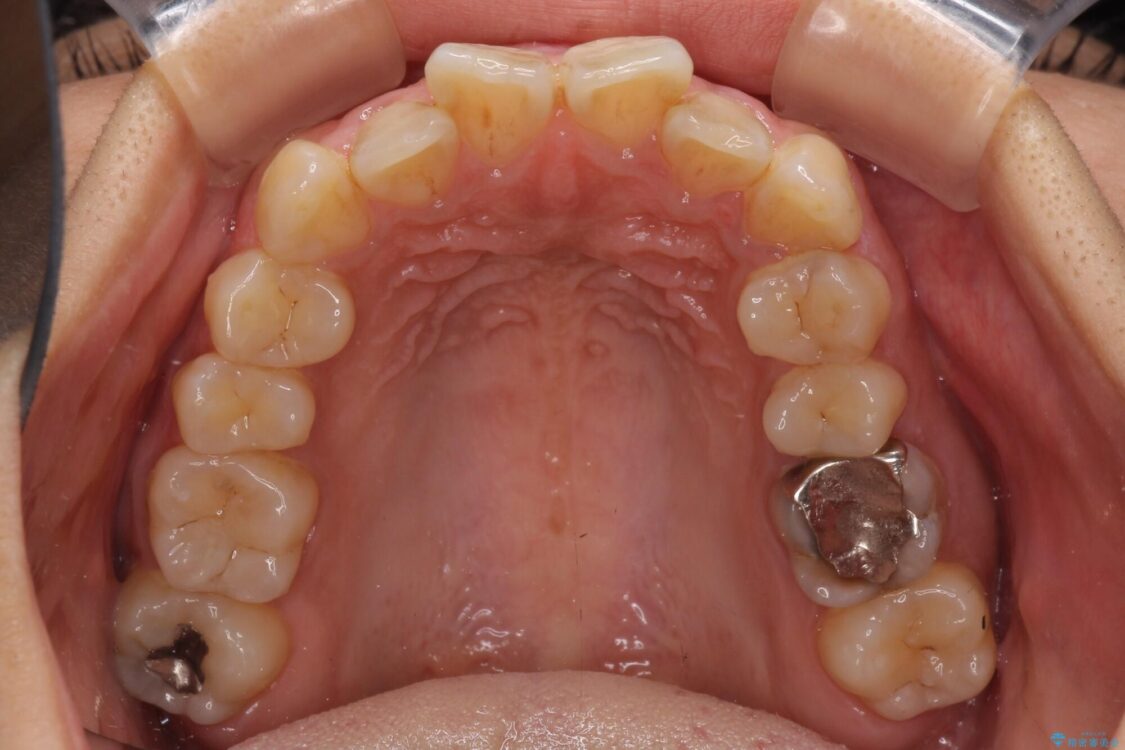

前歯のデコボコと上顎の前突感による口の閉じにくさを気にして来院された患者様です。

目立たない装置を希望されたので、上顎が裏側装置のハーフリンガルを選択し、上下左右の小臼歯(計4歯)を抜歯して矯正治療を行うこととしました。

治療前

• デコボコと口元の突出感 ハーフリンガルでの抜歯矯正 治療前画像